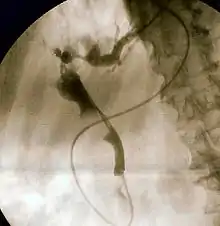

Duodenoscopy image of pus extruding from the ampulla of Vater, indicative of cholangitis

The gold standard test for biliary obstruction is still endoscopic retrograde cholangiopancreatography (ERCP). This involves the use of endoscopy (passing a tube through the mouth into the esophagus, stomach and thence to the duodenum) to pass a small cannula into the bile duct. At that point, radiocontrast is injected to opacify the duct, and X-rays are taken to get a visual impression of the biliary system. On the endoscopic image of the ampulla, one can sometimes see a protuberant ampulla from an impacted gallstone in the common bile duct or the frank extrusion of pus from the common bile duct orifice. On the X-ray images (known as cholangiograms), gallstones are visible as non-opacified areas in the contour of the duct. For diagnostic purposes, ERCP has now generally been replaced by MRCP. ERCP is only used first-line in critically ill patients in whom delay for diagnostic tests is not acceptable; however, if the index of suspicion for cholangitis is high, an ERCP is typically done to achieve drainage of the obstructed common bile duct.[1]